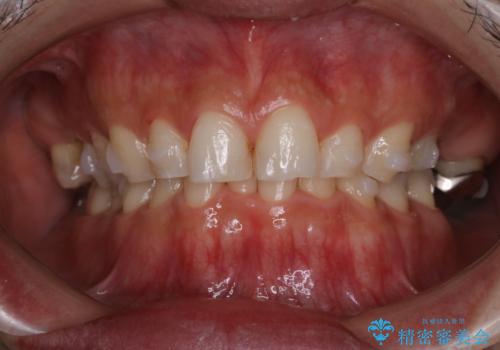

インビザラインでのマウスピース矯正中にPMTCでステインの除去

- インビザラインでの矯正治療中に着色を取るクリーニンングも行いたいとのことでした。PMTC30分コースを行いました。